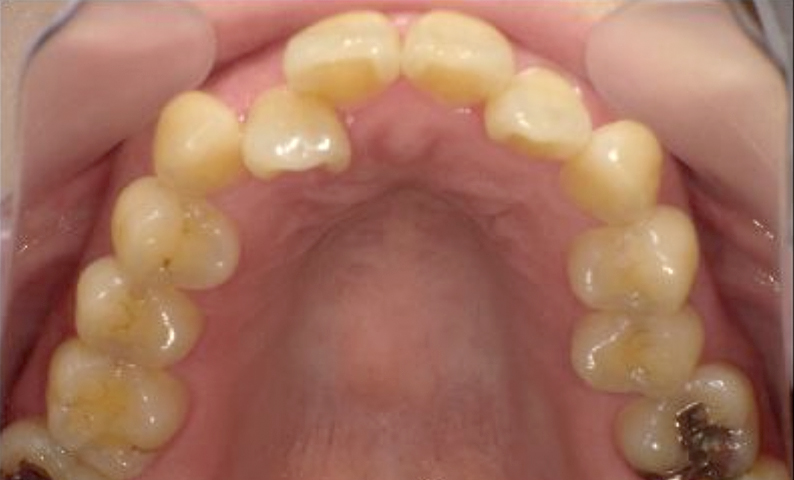

症例_002 下顎だけの部分矯正

治療期間:6ヶ月金額:21万円+税女性前歯のデコボコ下の前歯だけ